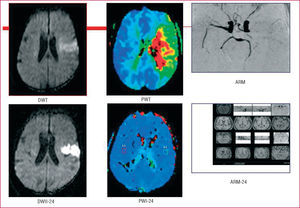

Respecto al infarto cerebral, su causa final es la falta de irrigación de sangre a cualquier parte del cerebro, lo cual produce isquemia y, en última instancia, infarto (muerte de células cerebrales). Cuando el tejido cerebral está isquémico ya se produce alteración de la función cerebral y, por lo tanto, las manifestaciones clínicas típicas de un ictus. La zona de tejido isquémico pero no infartado se conoce como zona de penumbra isquémica, y con tratamientos recanalizadores y cuidados adecuados es potencialmente salvable. Hoy día es posible visualizar, mediante técnicas de neuroimagen, resonancia magnética (RM) con difusión/perfusión y tomografía computarizada (TC) de perfusión, el tejido de penumbra isquémica o mismatch.

La resonancia magnética craneal (RM-C) resulta muy útil en el tratamiento del ictus, no sólo porque ayuda a confirmar y localizar topográficamente los infartos, sino también por su utilidad en su tratamiento agudo. En la actualidad se dispone de secuencias de difusión (DWI) que nos muestran el tejido infartado en la fase aguda, y mediante secuencias de perfusión (PWI) podemos cuantificar la extensión del tejido hipoperfundido; la diferencia entre ambas zonas nos identificará el tejido en penumbra o mismatch y, por lo tanto, potencialmente recuperable con tratamientos recanalizadores (fig. 3). Se recomienda la RM-C para localizar y confirmar infartos lacunares y para valorar el ictus de territorio vertebrobasilar. Se recomienda completar el estudio con angio-RM o, excepcionalmente, con arteriografía por sustracción digital (DIVAS), cuando se detecte por Doppler de los troncos supraaórticos/TC una estenosis en la arteria carótida interna > 50% o cuando se sospeche una estenosis intracraneal.

Fig. 3. Penumbra isquémica o mismatch. Ictus isquémico en el territorio de la arteria cerebral media, con oclusión de la arteria en la angiorresonancia magnética. Imagen en difusión (DWI) de la lesión de infarto y área de penumbra detectada mediante imagen de perfusión (PWI) correspondiente al área isquémica. La diferencia entre ambas zonas constituye el área de penumbra o mismatch. Control a las 24 horas con recanalización arterial y recuperación del área de penumbra con lesión residual en DWI.